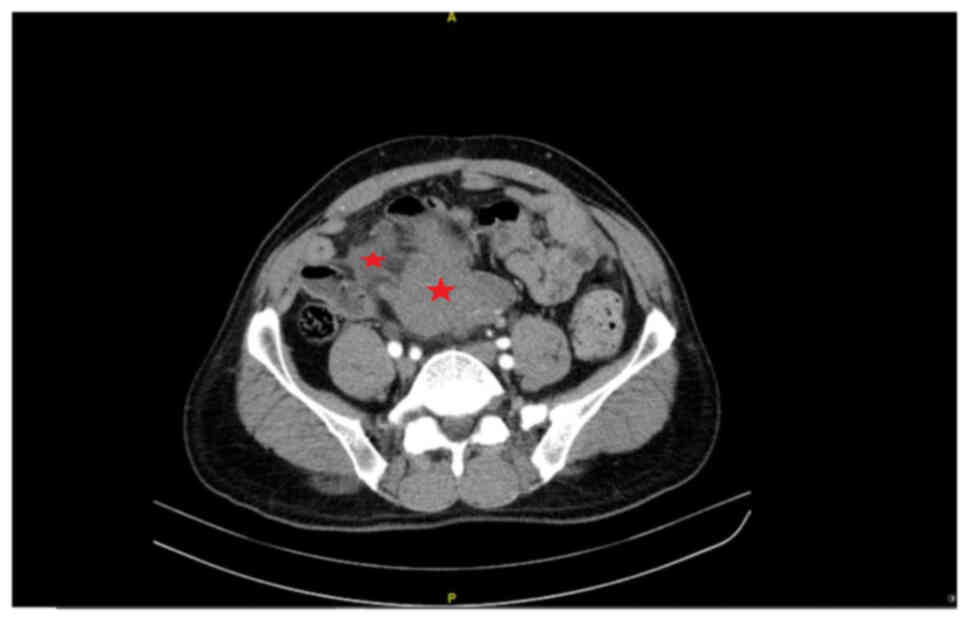

A 67-year-old male patient underwent retroperitoneal benign SFT resection at the Tianjin Medical University Cancer Institute and Hospital (Tianjin, China) in February 2009. The first recurrence presented as a malignant SFT in January 2018 and the second retroperitoneal tumor resection was performed in March 2018 at the Peking University International Hospital (Beijing, China). A total of 4 months after the second surgery, the second recurrence occurred and 40 months later the patient had hematochezia for 2 months. CT revealed multiple retroperitoneal masses involving the intestinal wall (Fig. 1). Immediately, the third retroperitoneal tumor resection (including part liver, intestine, mesentery and omentum resection) was performed at the Peking University International Hospital in November 2021. However, a number of small lesions could not be completely removed. The total size of the resected masses was ~18×18×8 cm, partially encapsulated with a smooth fibrous surface. The cross-section of the tumor showed lobulated white-brown areas (Fig. 2). Specimens were fixed with 4% formalin at room temperature for 12 h, embedded in paraffin, cut into 4-µm sections, stained for 5 min at room temperature with hematoxylin and eosin, and observed under a light microscope (Nikon Corporation). At the microscopic level, the short spindle-shaped tumor cells were arranged alternatively with hypocellular and hypercellular patterns separated by thick collagen fibers and blood vessels in the interstitium (Fig. 3). Compared with the previous postoperative specimens from the Tianjin Medical University Cancer Institute and Hospital, the hypercellular regions of the lesions presented obvious cytological atypia, increased mitoses count of 6–8 per 10 high power fields, and focal necrosis. The tumor encroached the surrounding liver, the whole layer of the intestinal wall and lymphatic vessels (Fig. 4). Two lymph nodes (2/18) showed the same histological finding as the hypercellular area (Fig. 5). In addition, multiple tumor nodules were seen in the mesentery and omentum.